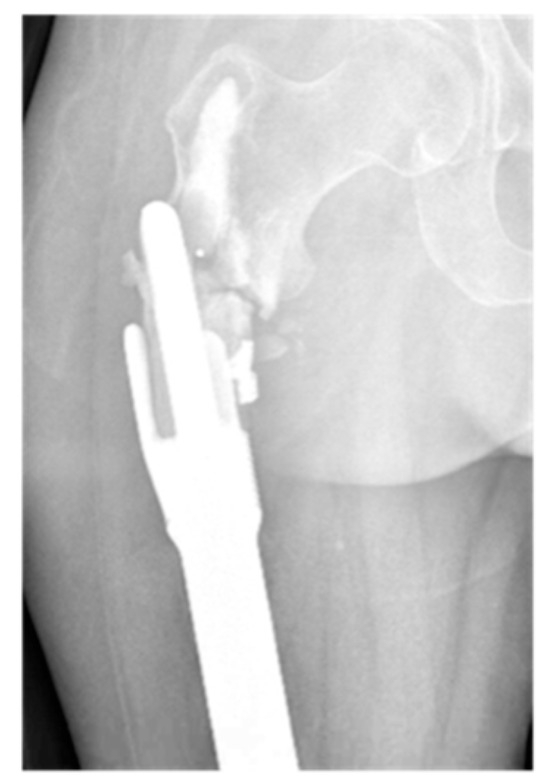

| Grade of loosening | |

| Grade 2 | 5 (17.9) |

| Grade 3 | 16 (57.1) |

| Grade 4 | 2 (7.1) |

| Grade 5 | 1 (3.6) |

| Grade 6 | 4 (14.3) |